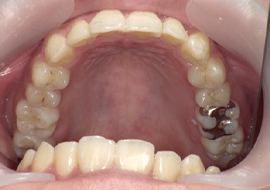

症例4

Before

After

| 主訴 | 上下前歯のがたつき |

|---|---|

| 年齢 | --- |

| 治療 期間 |

約9ヶ月 |

| 治療 内容 |

インビザラインiGoで上下顎の治療。 |

| 治療費 | ¥550,000(税込)/調整料含む |

| 治療のリスク | 矯正終了後は、リテーナーを指示通りに使用し、歯の後戻りを防ぐ必要があります。 |